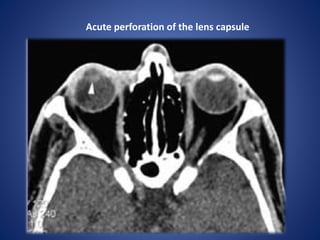

Acute perforation of the lens capsule

• #16 Axial CT. Acute perforation of the lens capsule. The abnormal lens (arrowhead) has low density due to the influx of fluid diluting the normally high protein of the lens. Compare with the opposite side.